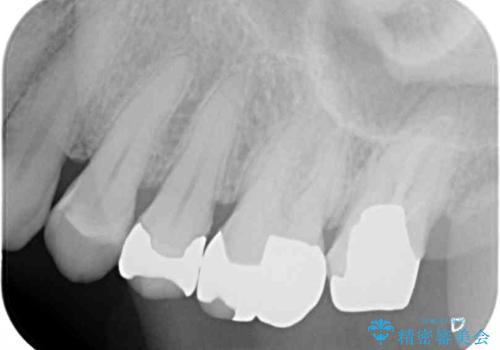

- 奥歯のクラウンが外れてしまったとのことで来院された患者様です。

土台の歯は、咬み合う下顎の歯と距離が近く、外れてしまったクラウンは、おそらく穴が空いてしまったのではないかと思われました。

距離が近いこと以外、特に大きな問題は認められなかったため、ゴールドクラウン(PGAクラウン)にて補綴することとしました。